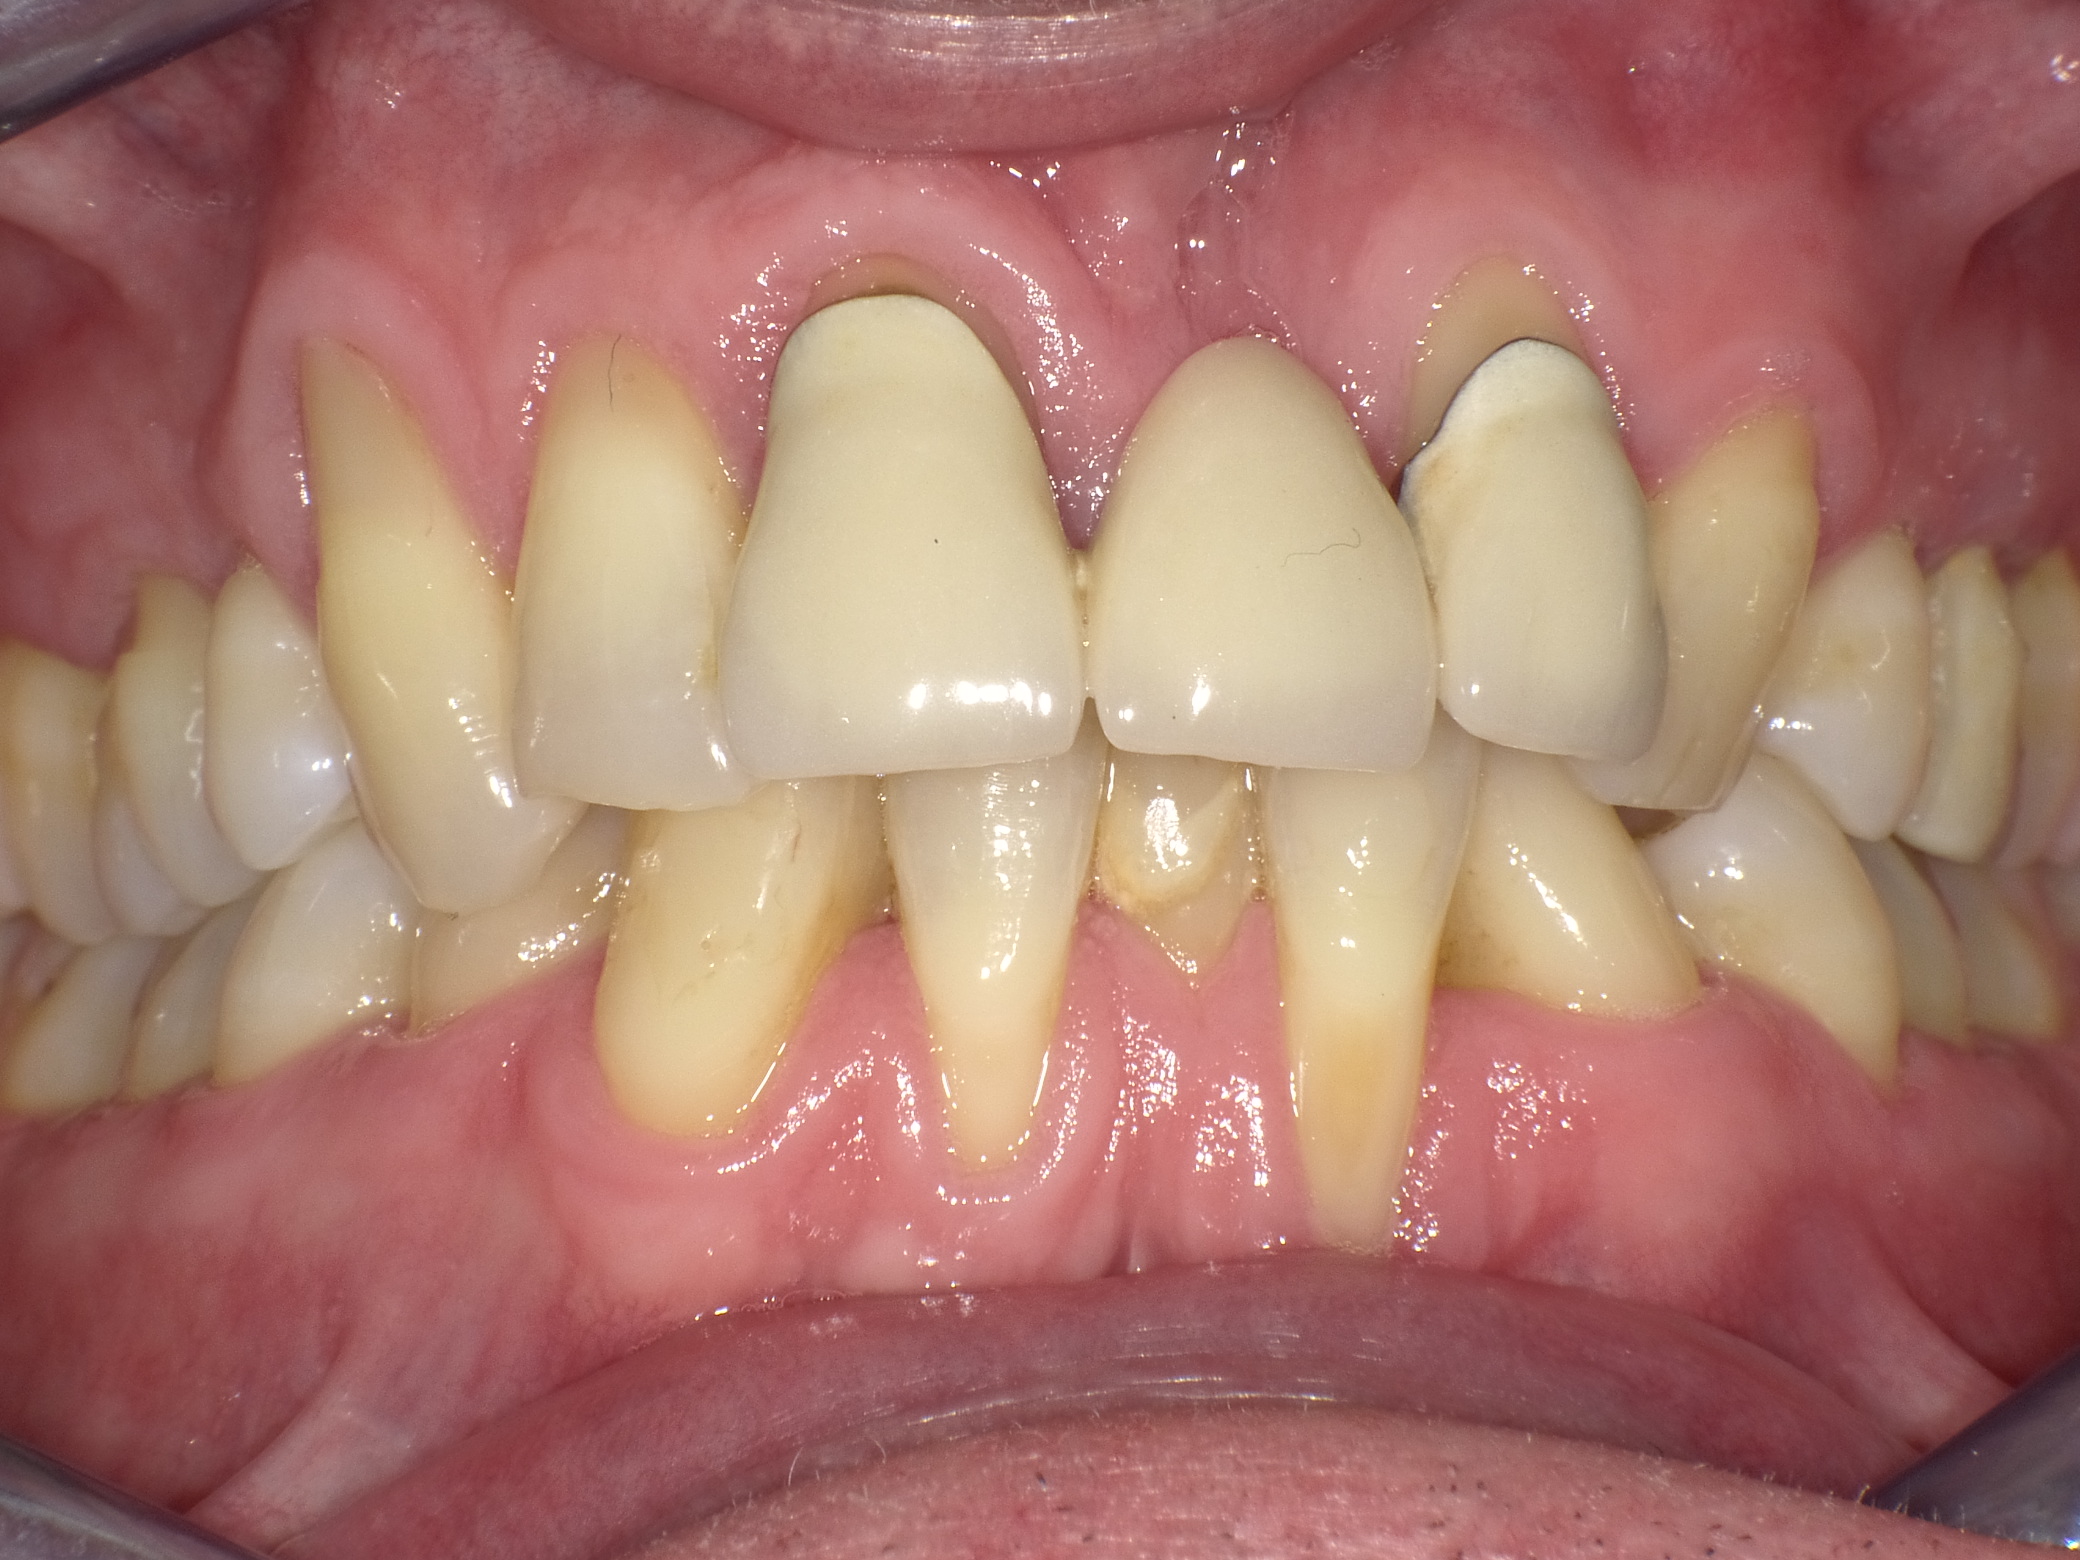

Unbefriedigende Ästhetik, vor allem aber Entzündungen im Knochen und eine massive Parodontitis mit bereits gelockerten Zähnen

Vorher: Unbefriedigende Ästhetik, vor allem aber Entzündungen im Knochen und eine massive Parodontitis mit bereits gelockerten Zähnen

Gesamtbehandlung in Sedierung: die Seitenzähne wurden durch Keramik-Implantate (Zahnentfernungen und Sofortimplantation) mit Knochenaufbau ersetzt; anschließend Gesamtüberkronung aus Vollkeramik mit Optimierung der Ästhetik

Nachher: Gesamtbehandlung in Sedierung: die Seitenzähne wurden durch Keramik-Implantate (Zahnentfernungen und Sofortimplantation) mit Knochenaufbau ersetzt; anschließend Gesamtüberkronung aus Vollkeramik mit Optimierung der Ästhetik